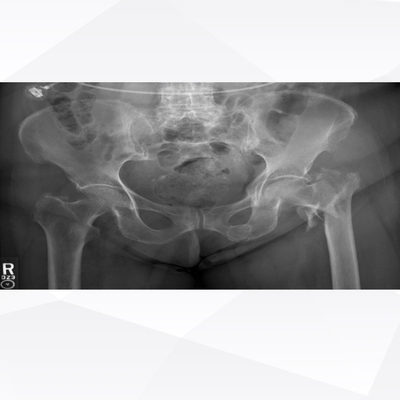

Click on an image below to view more info.